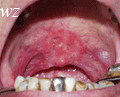

口腔颌面部常见肿瘤图谱

颌面部肿瘤图片(2)ppt